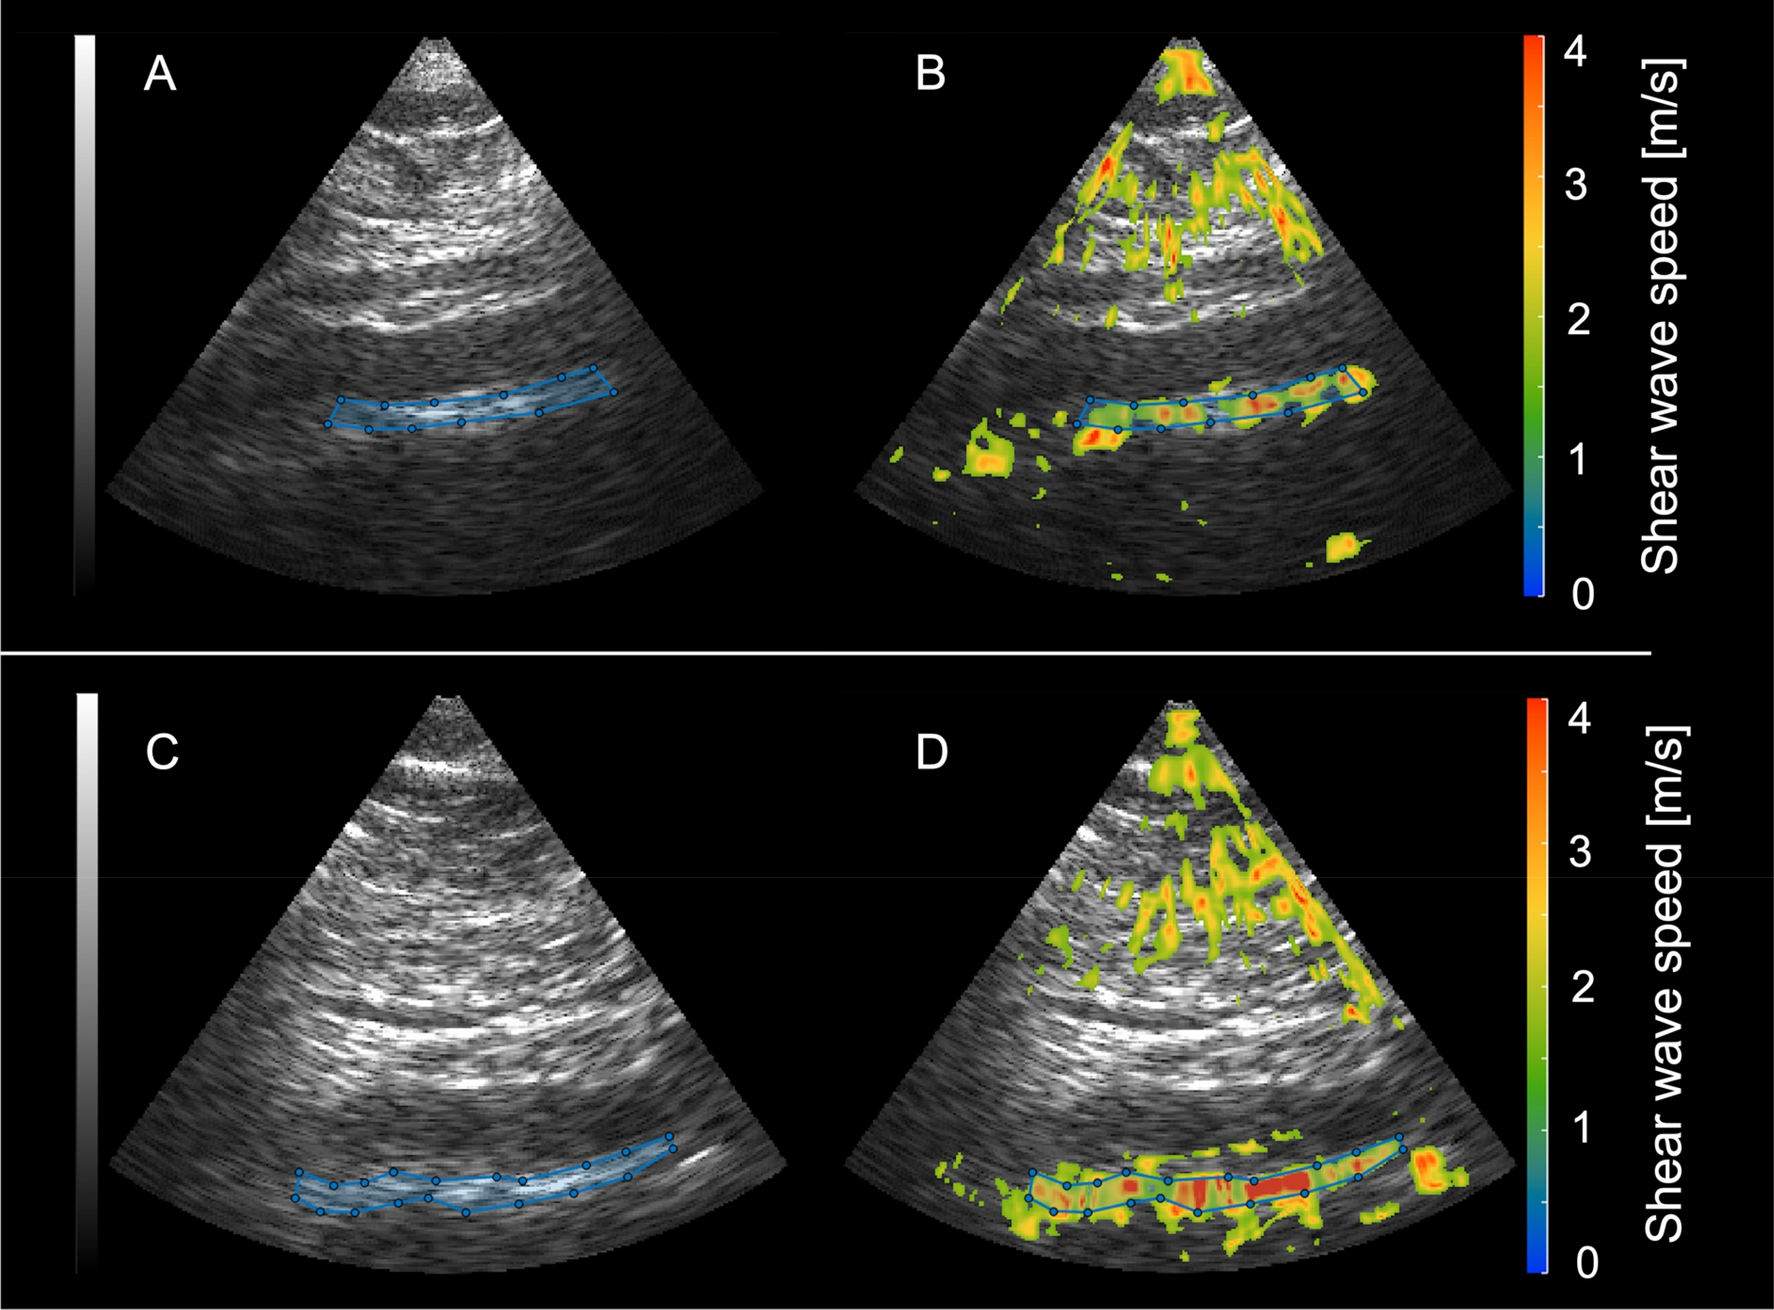

Sagittal B-mode images of the abdominal aorta and corresponding elastograms. The top row shows a sagittal B-mode image of the abdominal aorta (A) and the shear wave speed map (measured SWS: 2.77 m/s) (B) of a healthy non-smoking volunteer. The bottom row shows the corresponding B-mode image (C) and SWS map (measured SWS: 3.03 m/s) (D) of an age-matched smoker.